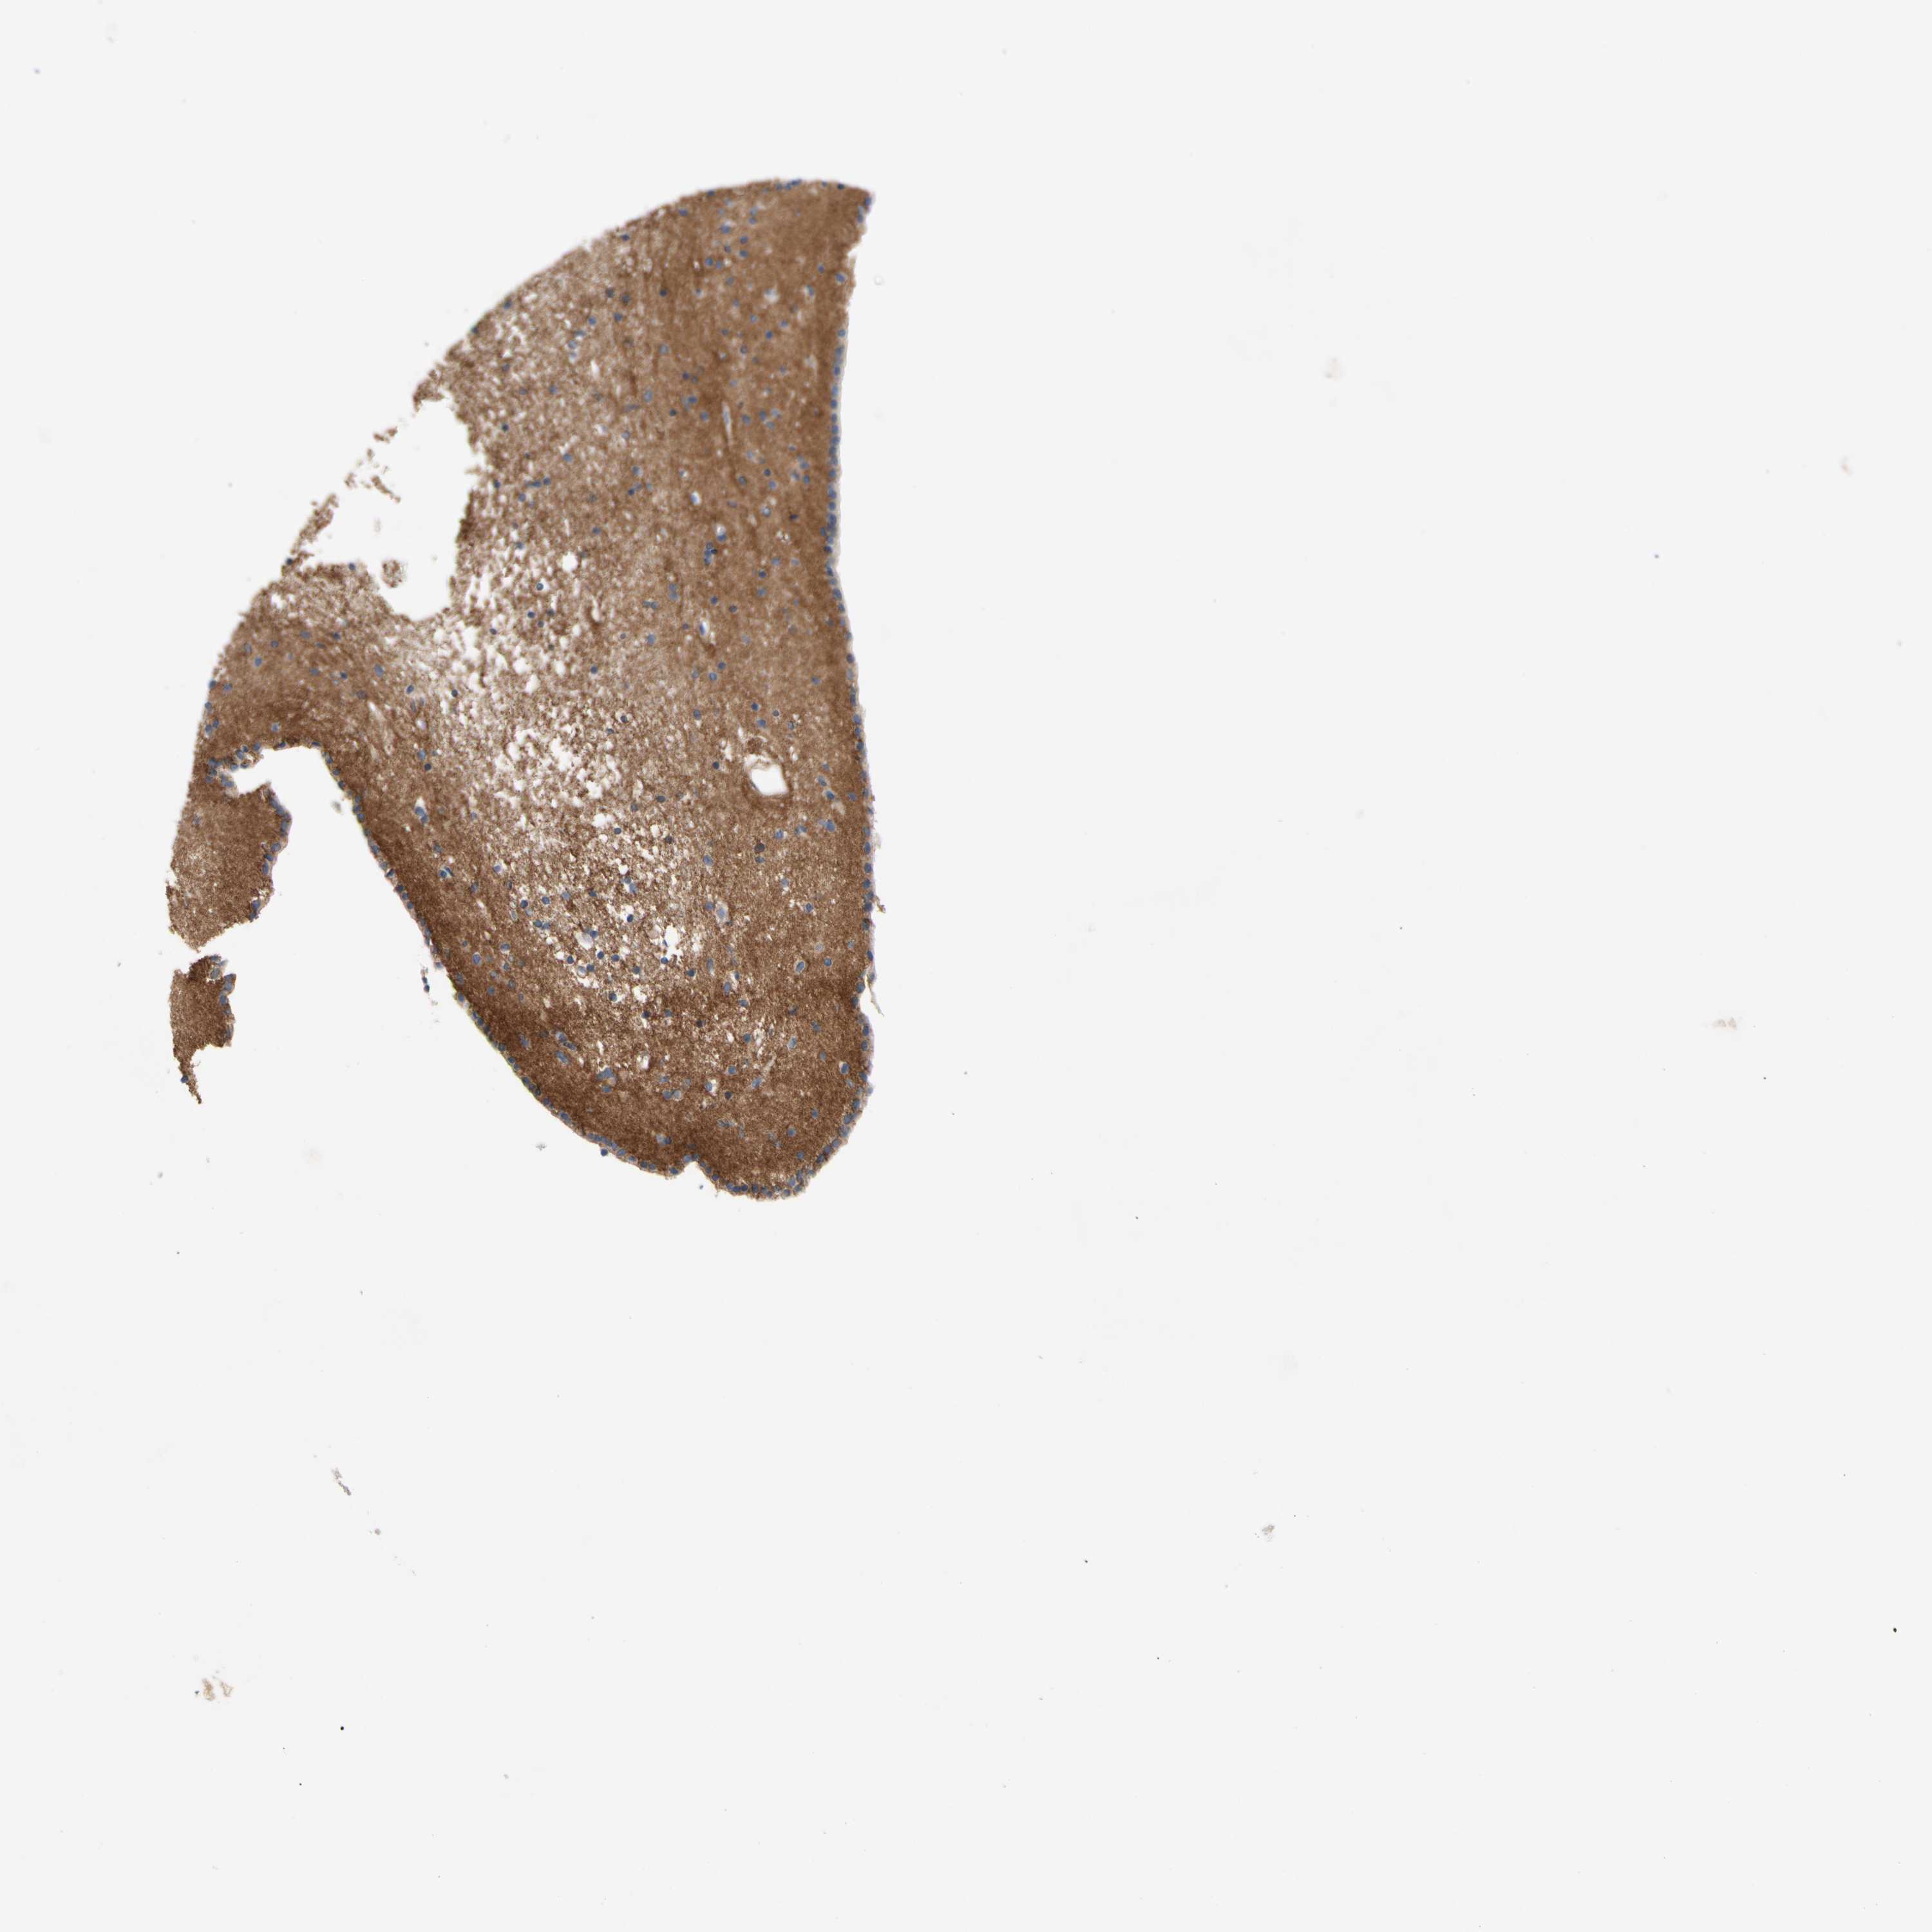

Antibody staining in the annotated cell types in the current human tissue is reported as not detected, low, medium, or high. This score is based on the staining intensity and fraction of stained cells.